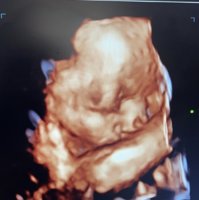

Eve ja i mojata lepotica ama denska 29 nedeli uste ne mozeme raceto od lice da mu e izvajme

Прикачени фајлови: